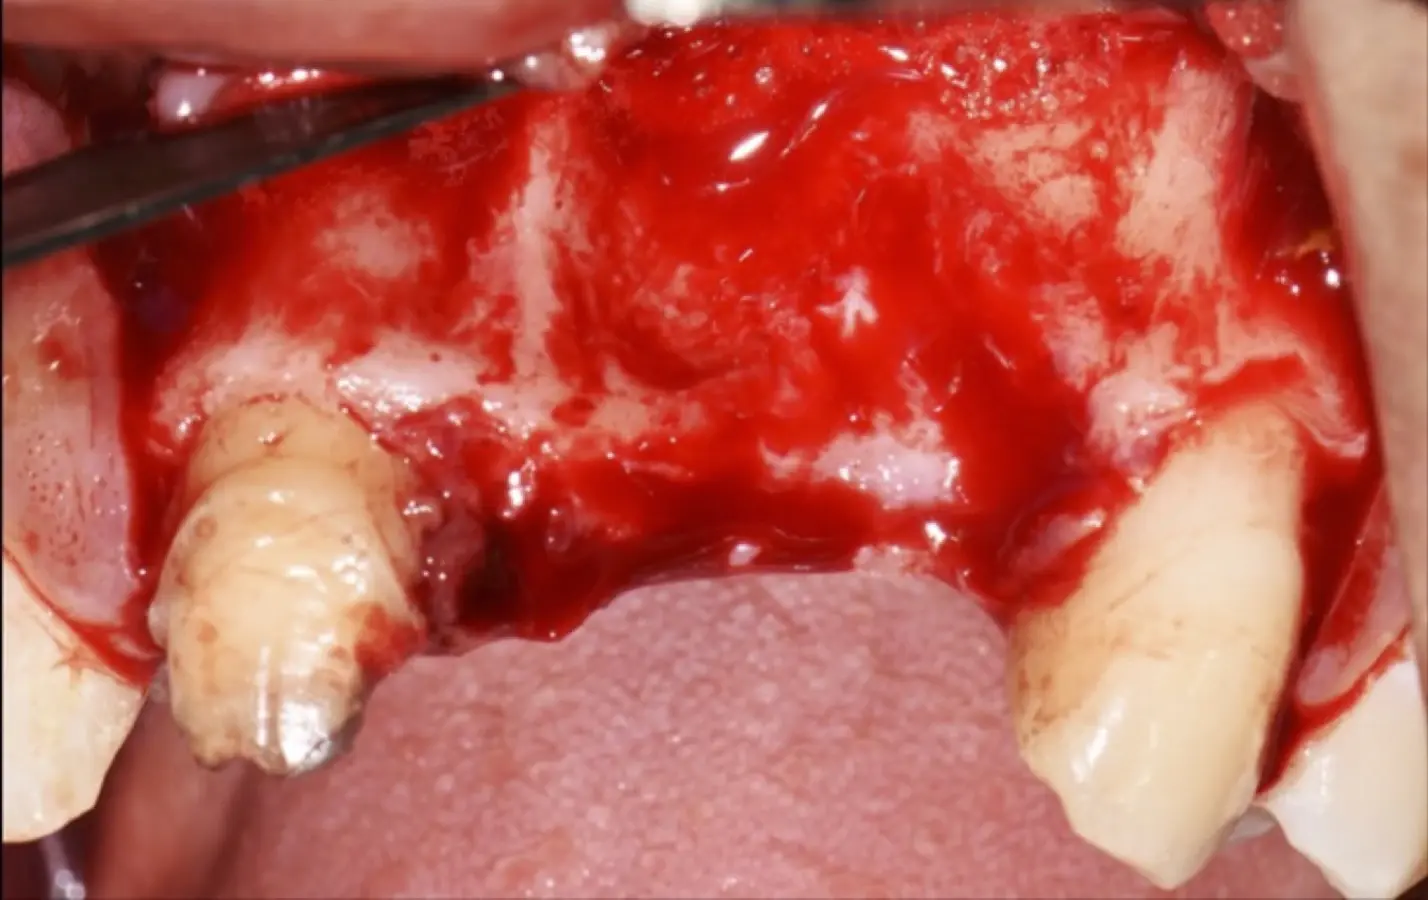

Los casos clínicos que presentamos a continuación muestran claramente las ventajas del piezoeléctrico en diversos procedimientos de terapia ósea regenerativa. En el primer ejemplo, una reconstrucción de reborde con injertos en bloque previo a la planificación de implantes dentales en un caso de edentulismo total superior con una severa reabsorción ósea. En el segundo ejemplo se utilizó esta tecnología para la reconstrucción de lechos para implantes de estructuras óseas con hueso en bloque de origen bovino y posteriormente la colocación de implantes dentales. Los dos casos son parte del capítulo 9 del libro “Cirugía piezoeléctrica: generalidades y aplicaciones clínicas”.